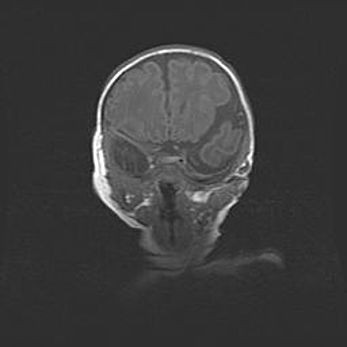

Лейкомаляция с кистозно-глиозной дегенерацией головного мозга.

Возраст: 2 месяца 25 дней

Вес: 6400 г

Окружность головы: 40 см

Срок гестации: 41 неделя

Лейкомаляцию относят к ишемически-гипоксическим повреждениям головного мозга, диагностируемым у новорожденных. При лейкомаляции в головном мозге обнаруживают очаги некроза, возникшие после тяжелой гипоксии и нарушения кровотока. В процессе морфогенеза очаги проходят три стадии: 1) развития некроза, 2) резорбции и 3) формирования глиозного рубца или кисты. Перивентрикулярная лейкомаляция (ПЛ) встречается примерно в 12% случаев среди новорожденных, обычно – у недоношенных детей, причем, частота ее зависит от массы, с которой младенец появился на свет. Наибольшее число малышей страдает лейкомаляцией, если масса при рождении 1500-2500 г.